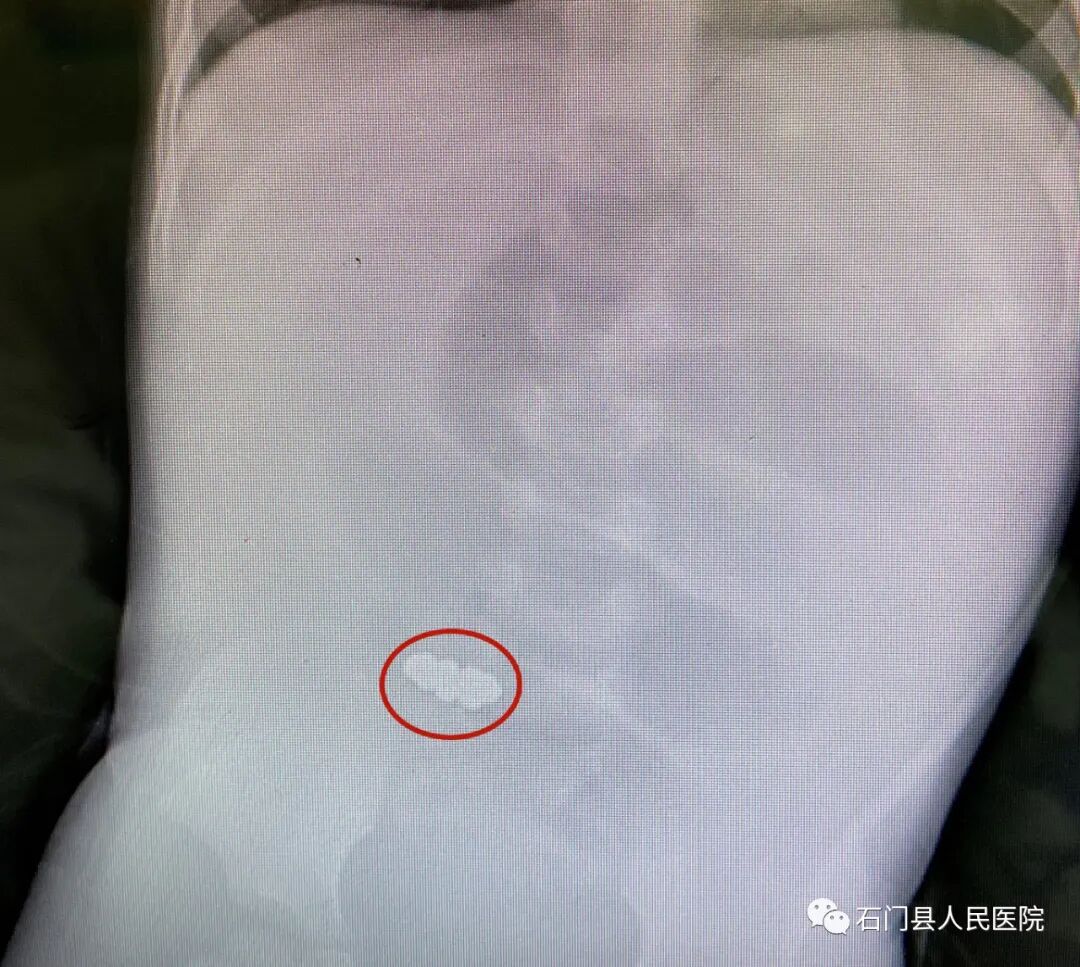

同时术中在肠内取出了导致林林肠穿孔的罪魁祸首——9颗磁力珠!

→从林林肠道内取出的磁力珠。

近些年,磁力珠玩具非常流行,但是因磁力珠造成的伤害也层出不穷,医生介绍,磁力珠不同于普通的异物,珠子因磁力吸引相互连在一起夹挤肠管,所以它们不会像硬币、螺丝帽等随着大便排出,反而都会导致肠穿孔一旦穿孔后的肠内容物溢出至腹膜腔,可能会引起弥漫性腹膜炎,除了剧烈腹痛、腹胀等症状,严重的会导致休克甚至死亡。所以对没有判断能力的孩子来说,磁力珠是很危险的玩具。